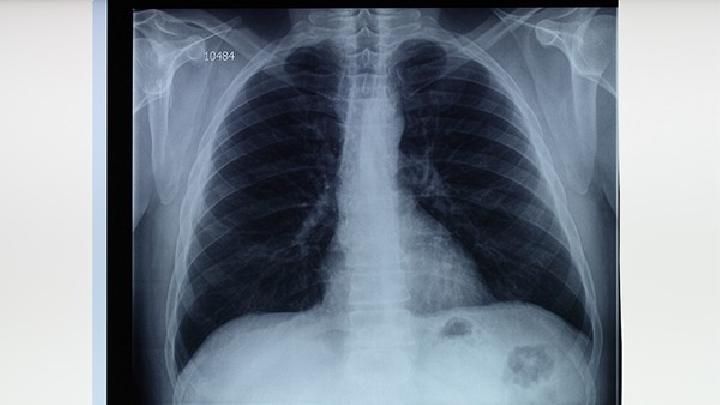

2.发型 又称儿童-成人型。多见于免疫功能低下或有缺陷的人群。发烧、咳嗽、呼吸困难、发绀等疾病迅速发生,但声音很少。病程短的人可以4~8天内死亡。X线胸部变化常迟于临床表现。如无特效治疗,无论成人或儿童,病死率高达90%~100%。两种肺X线性表现为弥漫性、双侧条索或斑点阴影。肺炎和肺底受累较少。它可以迅速发展,导致肺实变。实变病变中常有广泛或局限性肺气肿后小段肺不张。有些病例可见气胸、胸水、肺结节阴影等。动脉血氧分压通常低于10.7kPa(80mmHg),C02正常或低分压,动脉血pH常增高。